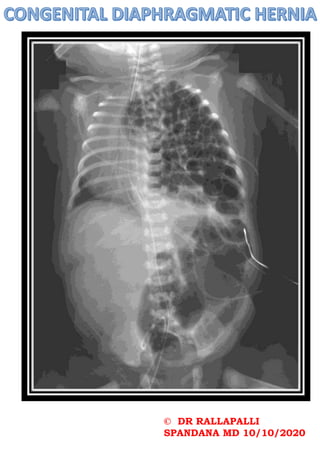

•indistinct diaphragm with

opacification of part of or all

the hemithorax (typically left

sided)

•scaphoid abdomen

Congenital diaphragmatic herniation

can be classified into two basic types

on location:

1.Bochdalek hernia

1. most common fetal congenital

diaphragmatic hernia

2.commoner on the left: 75-90%

3.posterolateral

4.large and associated with poorer

outcome

5.presents earlier

6.mnemonic: BBBBB

2.Morgagni hernia

1. less common

2.anterior

3.presents later